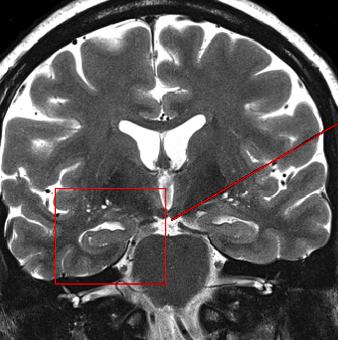

头部MRI:被久坐影响的大脑

感觉罪恶吗?如果是,我还有一些坏消息。

在这项研究中,久坐与大脑皮质变薄有关。就是这样。

这个大脑区域被称为内侧颞叶,它在认知和情感功能中发挥作用。

这意味着久坐可能是认知能力下降和痴呆发生的前因。